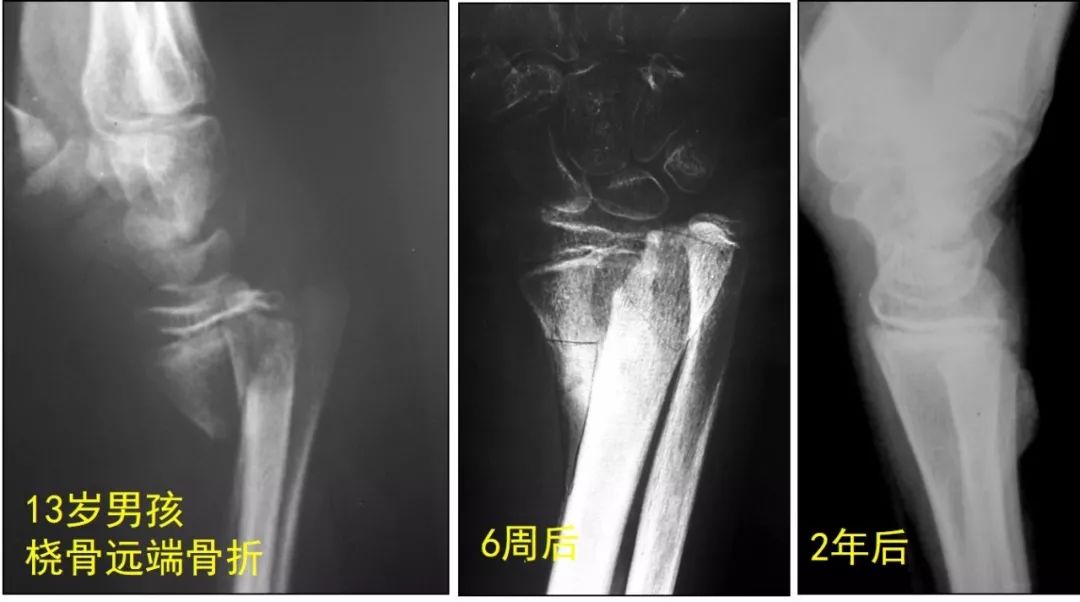

儿童骨折塑形能力图

儿童骨折塑形能力图,儿童骨折的照片真实

广州操医生专栏:儿童骨折一定要手术吗?

断端完全错位,通过简单锁骨带固定,半年后骨折愈合,自我塑形(图3)

孩子和成人区别很大,骨折后有非常强大的塑形潜力,年龄越小这种塑形

愈合和塑形能力,故大部分儿童的尺桡骨远端骨折均可采用保守治疗(图1